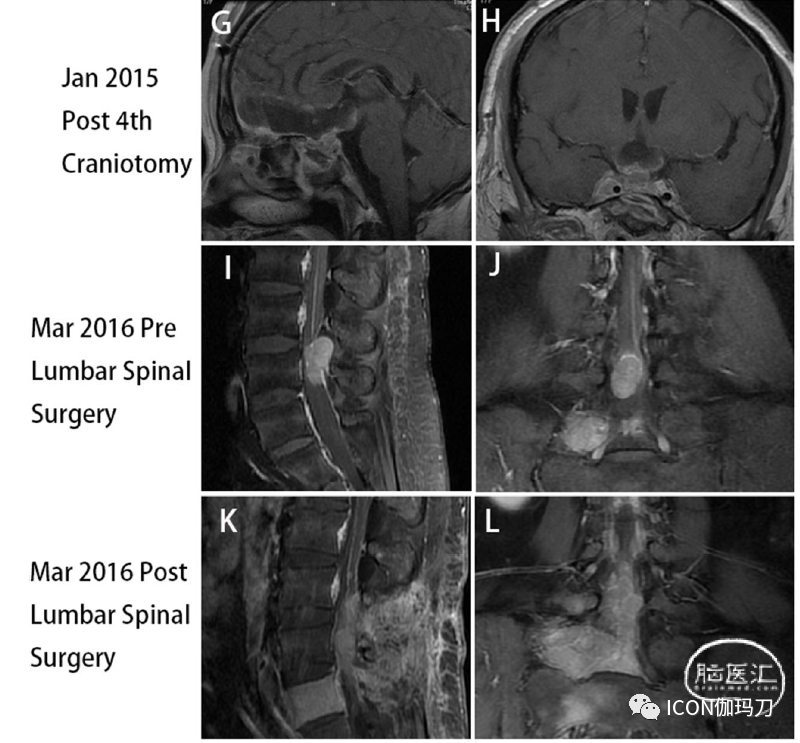

她经历了左眼视力丧失,MRI报告肿瘤体积显著增加,并压迫视交叉(图3E和F),血清泌乳素水平升至200.0 ng/ mL(未稀释样本)(补充图1)。行第四次经颅垂体瘤次全切除术(图3G和H);然而,视力下降没有改善,术后出现中枢系统感染。经抗生素治疗及腰椎引流后,中枢系统感染治愈。垂体肿瘤切除后的病理结果显示Ki-67指数增加到20%(图4F)。2016年3月,她面对痛苦和软弱的右腿,和MRI显示硬膜内的类似质量的第四腰椎(图3 I和J)。全身ECT等报道,多个高代谢(hypermetabolic)焦点被发现在第五腰椎(补充图2),血清泌乳素水平再次升至200.0 ng/mL(标本未稀释)(补充图1)。经后路硬膜外病变完全切除(图3K和L)。术后右腿疼痛和无力明显恢复。但血清泌乳素水平没有显著下降(补充图1)。切除的椎管内肿瘤的组织学检查显示,免疫组化(IHC)PRL为强阳性,而其他垂体激素为阴性。Ki-67指数上升到30%(图4H和I)。病理结果与分泌泌乳素垂体癌(PCs)的转移一致。随访期间,血清泌乳素水平持续升高,2016年10月最后一次血清泌乳素检测结果为356.0 ng/mL(补充图1)。不幸的是,鞍区肿瘤继续快速进展,患者于2017年10月死亡。

图3.(A)和(B)在第三次经额开颅前,2014年10月MRI显示肿瘤迅速扩大,鞍上延伸并包绕右侧ICA。(C)和(D)第三次开颅后,将肿瘤近全切除。(E)和(F)第四次经额开颅前,2015年1月MRI报告肿瘤体积明显增加,并压迫视交叉。(G)、(H)第四次开颅后,肿瘤次全切除。(I)和(J)腰椎MRI显示第四腰椎水平硬膜内髓外肿块。(K)和(L)术后MRI提示硬膜内髓外病变完全切除。